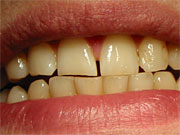

Durch

Zähneknirschen (Bruxismus) abgeschliffene

obere Schneidezähne

Schneidezähne sehen so aus, sind alle gleich

hoch und haben ihr individuelles Aussehen

verloren.

Im

Gegensatz dazu haben normale Zähne leicht

unterschiedliche Formen und leicht

unterschiedliche Höhen